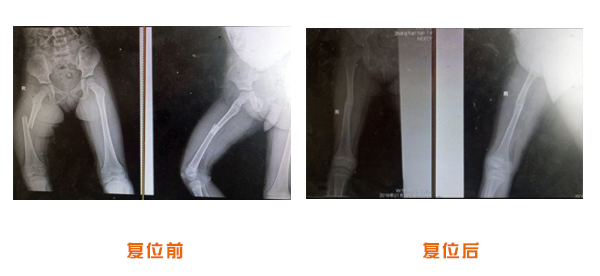

復位前后對比